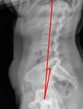

Thoracic Kyphosis (T5–T12 Cobb)

Sagittal Vertical Axis (SVA)

T1 Pelvic Angle (T1PA)